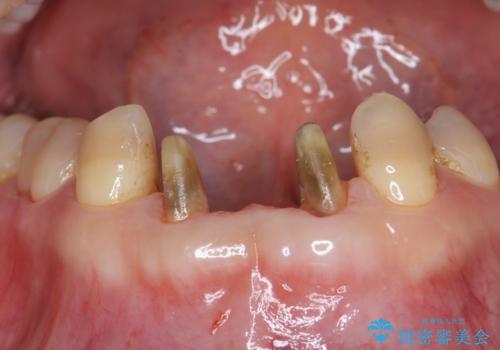

- 前歯の保険のブリッジが欠けてしまっているのを治したいとのことでした。

前装冠が剥がれていて、下の金属が見えてしまっていました。

保険のブリッジは入れてすぐ欠けてしまったのを長年使用していたとのことです。

かみ合わせもきつく、ジルコニアクラウンではセラミックでも欠けてしまいそうでした。

今回は、丈夫な欠けにくいフルジルコニア(ヴェレッツァ)クラウンでブリッジにすることにしました。